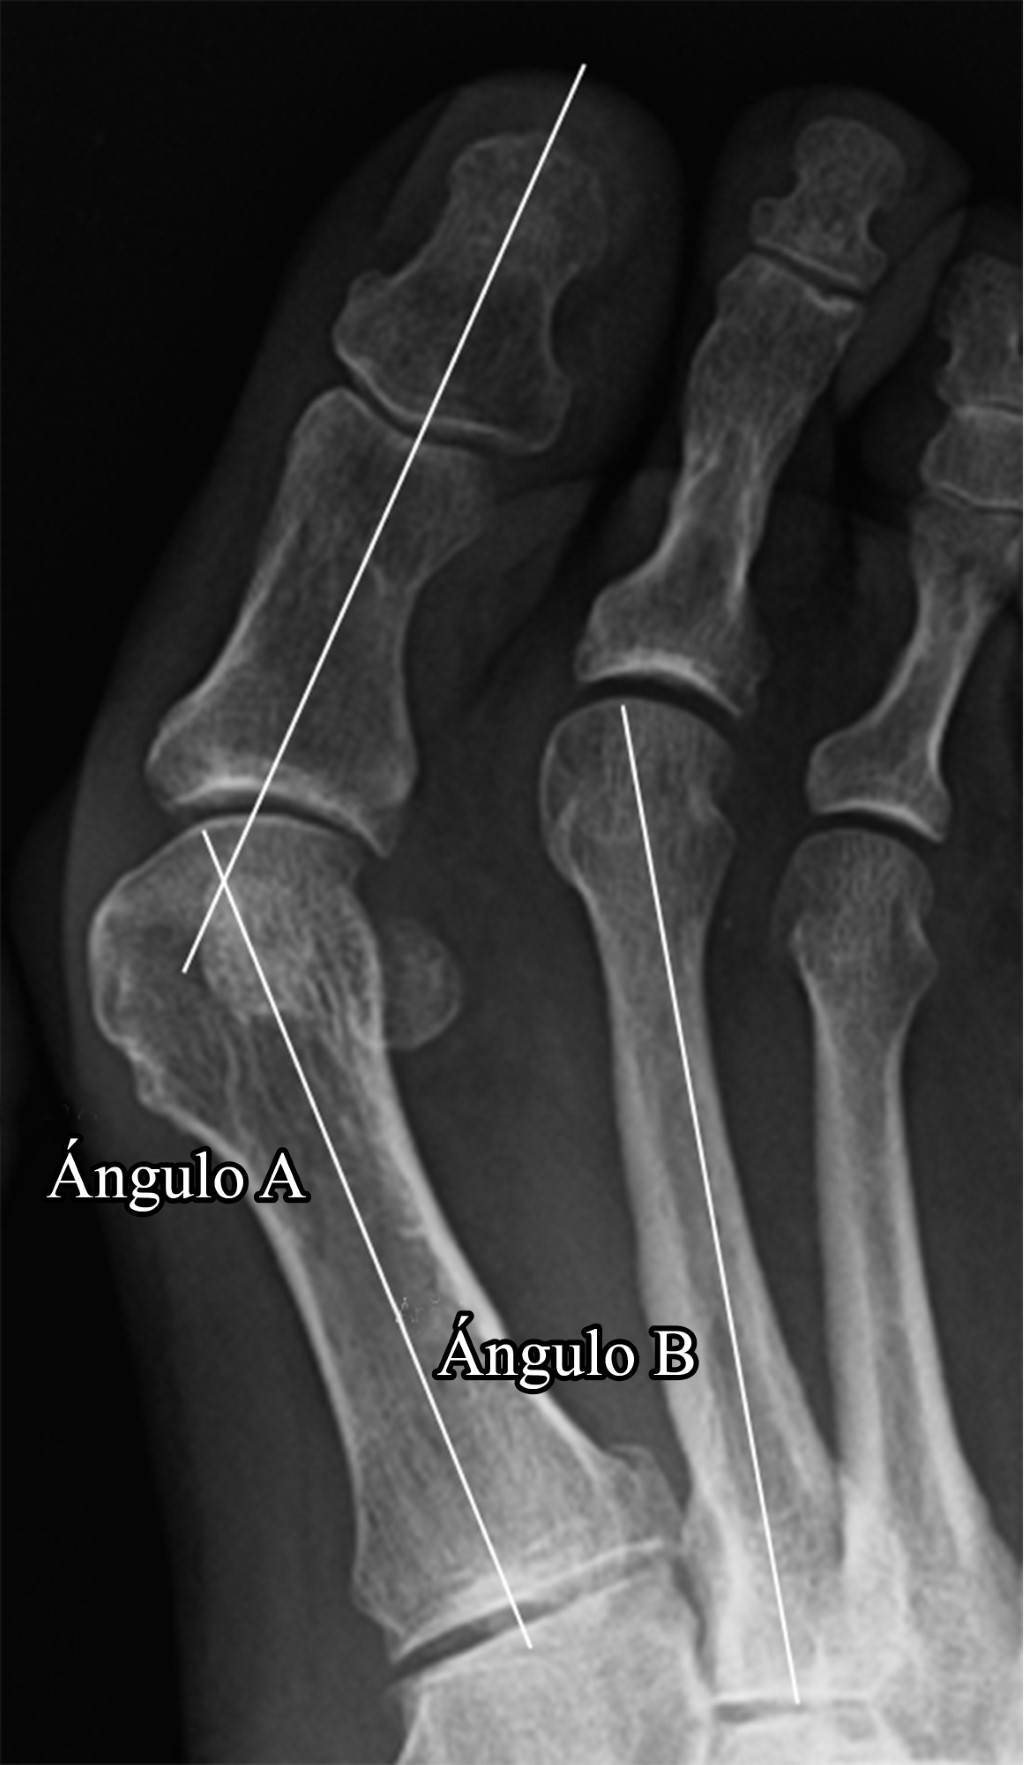

Las radiografías que se utilizaron para el estudio eran todas en carga y fueron revisadas retrospectivamente. El ángulo hallux valgus (AHV) y el ángulo intermetatarsiano (AIM) se midieron antes de la cirugía y a los tres meses de la misma. También se recogieron las complicaciones quirúrgicas, tales como el desplazamiento secundario de la osteotomía, la fractura del primer metatarsiano o la presencia de una seudoartrosis. Los datos se analizaron utilizando el sistema Raim Viewer (versión 2.5). La Figura 2 muestra el ángulo a correspondiente al AHV y el ángulo b que corresponde con el AIM.7

En cuanto al análisis radiológico, se registraron dos complicaciones, un desplazamiento secundario de la osteotomía y una fractura del primer metatarsiano, en el grupo ZSR (7%); mientras que en el grupo ZSI hubo sólo un caso de desplazamiento secundario de la osteotomía (3.4%). Los valores medios preoperatorios del AHV fueron de 36.9° ± 6.6 en el grupo ZSR y de 39.8° ± 9.4 en el grupo ZSI. A los tres meses de la cirugía, el AHV fue de 17° ± 8.5 en el grupo ZSR y de 22° ± 8.1 en el grupo ZSI. El AIM preoperatorio medio fue de 13.3° ± 3.3 en el grupo ZSR y de 14.9 o ± 4.3 en el grupo ZSI. El AIM medio a los tres meses postoperatorios fue de 9.3° ± 3.6 en el grupo ZSR y de 11.3° (3.6) en el grupo RCS (Figura 3A y B). No se encontraron diferencias estadísticamente significativas entre las complicaciones radiológicas postoperatorias, ni tampoco en los valores del AHV y AIM pre y postoperatorios.